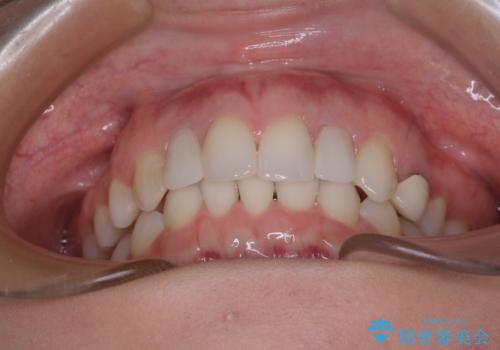

【モニター】前歯の変色とデコボコを改善 インビザラインとオールセラミック

- 前歯の歯並びと神経を取って変色してしまった前歯を気にして来院された患者様です。

上下前歯の歯列不正はインビザラインにより整え、その後に、前歯2本をオールセラミッククラウンにて補綴治療することとしました。

下顎前歯が1本欠損しており、下顎歯列の大きさが本来よりも小さいため、上顎歯列とのバランスが悪く、深い咬み合わせになっていました。

上顎にIPRを多用して歯列の大きさを小さくするよう試みましたが、理想的な咬み合わせまでには改善させることはできませんでした。